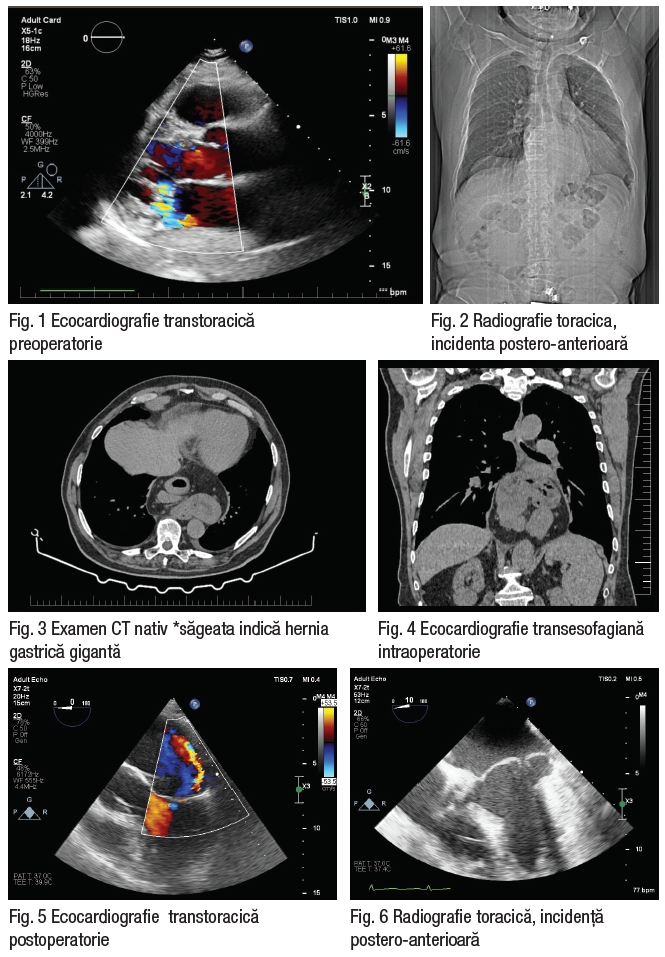

Unul din multiplele exemple în care chirurgia cardiacă minim invazivă are beneficiu major ar fi cel al unui pacient de 81 ani, cunoscut cu regurgitare mitrală severă simptomatică, regurgitare aortică și tricuspidă moderată, hipertensiune pulmonară ușoară, prezentat în clinica noastră pentru reevaluare și tratament de specialitate. Ecocardiografia transtoracică preoperatorie documentează un ventricul stâng dilatat și concentric hipertrofiat, cu funcție sistolică normală, fără tulburare de cinetică segmentară sau globală. Ventricul drept ușor dilatat cu funcție sistolică normală. Dilatare de atriu stâng (AS) semnificativă. Regurgitare mitrală severă cu jet excentric ce se mulează pe peretele posterior al AS, probabil ruptură de cordaj A2, prolaps A1-P1. Regurgitare aortică medie, Regurgitare tricuspidiană ușoară, (Fig. 1, 4). Prezintă un pat coronarian cu distribuție echilibrată, fără stenoze decelabile angiografic.

În cursul internării, pacientul a fost diagnosticat cu hernie gastrică transhiatală gigantă, diagnostic stabilit oportunist, urmare completării protocolului preoperator cu radiografie toracică (Fig. 2), ulterior – examen CT (Fig. 3).

Având în vedere accesul dificil prin sternotomie dat de anatomia particulară intratoracică și complicațiile respiratorii posibile s-a intervenit chirurgical și s-a practicat plastie valvulară mitrală prin scurtarea unui cordaj primar la nivel A2 și anuloplastie cu inel Physio II nr. 34, prin minitoracotomie dreaptă. Controlul intraoperator ecografic documentează plastie normofuncțională, funcție biventriculară păstrată, iar sevrarea de circulație extracorporeală fiind facilă. Evoluția postoperatorie a fost una favorabilă, pacient transferat pe secție în ziua 2 postoperator, stabil din punct de vedere hemodinamic și respirator, plagă în curs de vindecare. Radiografia de control și ecocardiografia denotă o evoluție paraclinică bună (Fig 5,6). Pacientul se externează în ziua 7 postoperator.